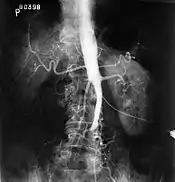

Fluoroscopic image of an aorta affected by Leriche's syndrome

The physical examination usually shows weakened femoral pulses and a reduced ankle-brachial index. The diagnosis can be verified by color duplex scanning, which reveals either a peak systolic velocity ratio ≥2.5 at the site of stenosis and/or a monophasic waveform. MRA and multidetector CTA are often used to determine the extent and type of obstruction. Another technique is digital subtraction angiography which allows verification of the diagnosis and endovascular treatment in a single session.[1]

Angiography provides important information regarding the perfusion and patency of distal arteries (e.g. femoral artery). The presence of collateral arteries in the pelvic and groin area is important in maintaining crucial blood flow and lower limb viability. However, angiography should only be used if symptoms warrant surgical intervention.[1]